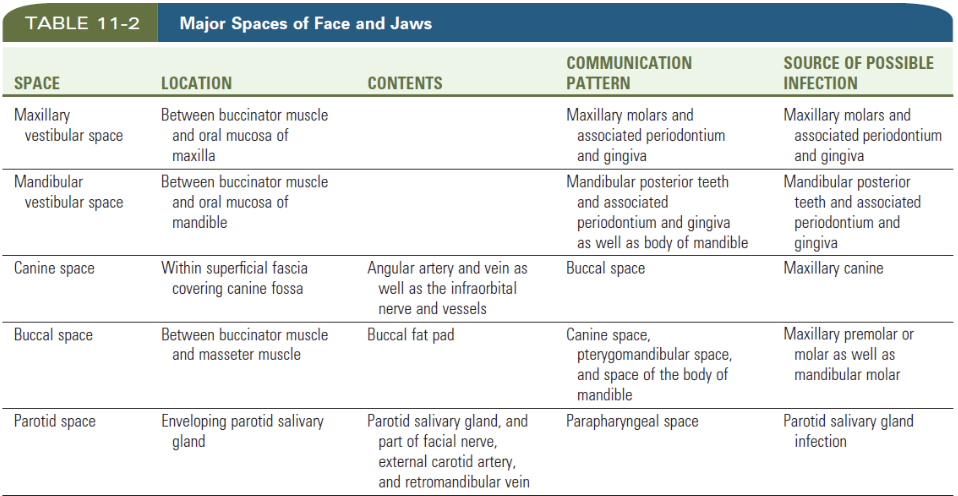

Space

Vestibular space

- of Maxilla

- of Mandible

Canine space (Maxilla)

- Nasolabial sulcus

Buccal space

- Buccal fat pad

- Parotid duct

- Facial a.

Parotid space

- Parotid g.

- Facial n.

- ECA

- Retromandibular v.